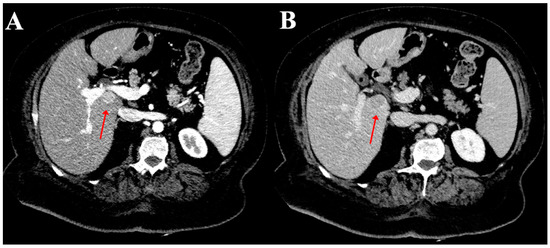

2.2. Image Analysis